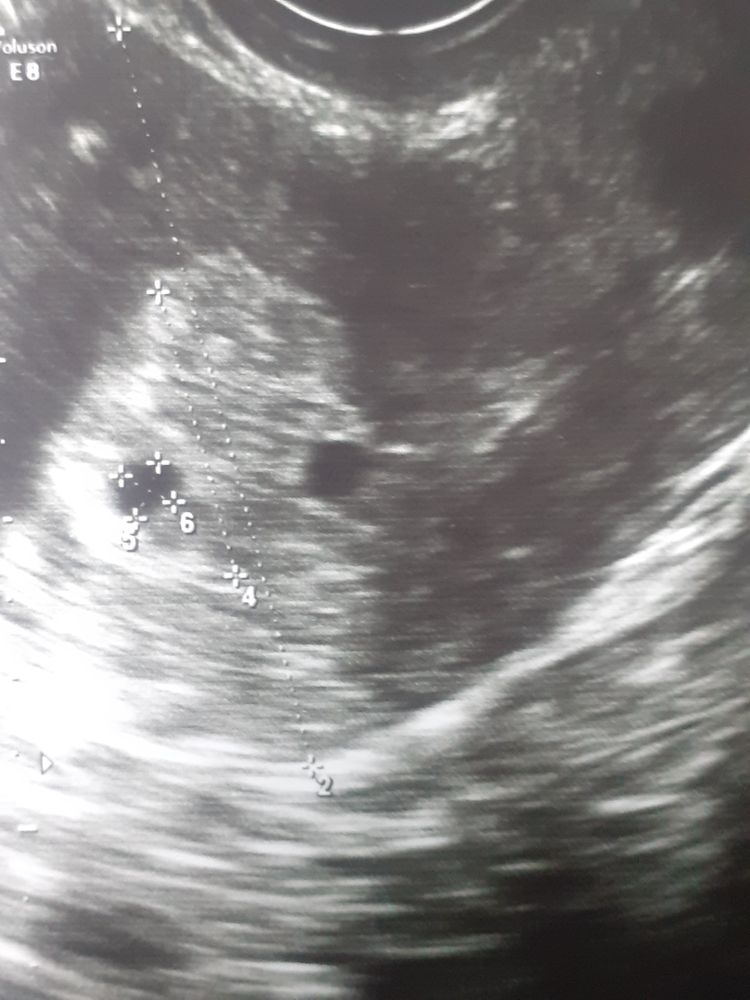

Ладно если бы у вас скрининг был уже с таким ростом,а сейчас все ещё шатко-валко,пя и жм по узи ещё не говорит о том,что беременность закончится родами,у меня тоже плохо рос хгч,сохраняла как могла,хотя наверное не стоило, изначально шло все не так,в 5 недель пя 3 мм,в 6 недель пя 6 мм и жм 3,в 7 недель пя 12,ктр 8 и сб+ но расслабляться рано было,не смотря на то, что эмбрион был и сердцебиение,но пя маленькое для срока,плохо росло,как и хгч,места в пя уже не было и через 5 дней уже и сб не было и закончилось чисткой,у вас судя по фото,пя тоже крохотное,но желаю удачи, готовьтесь к любому исходу